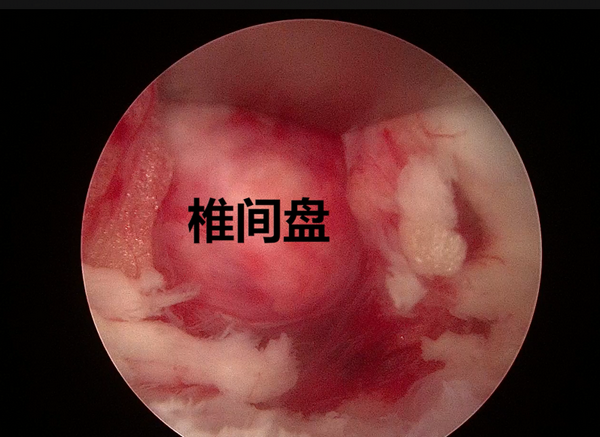

髓核摘除前后对比

切除后黄韧带和椎间盘髓核组织

4.显露椎间盘

5.摘除髓核